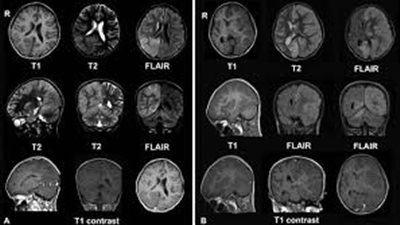

أكدت دراسة علمية، أجراها الباحث الفرنسي انطون بيس في مركز الدراسات الإستراتيجية الفرنسية، أن الانفعالات التي يتعرض لها الإنسان من فرح وغضب وحزن وحب ناتجة عن توازن لبعض المواد المختلفة في المخ خاصة في ...